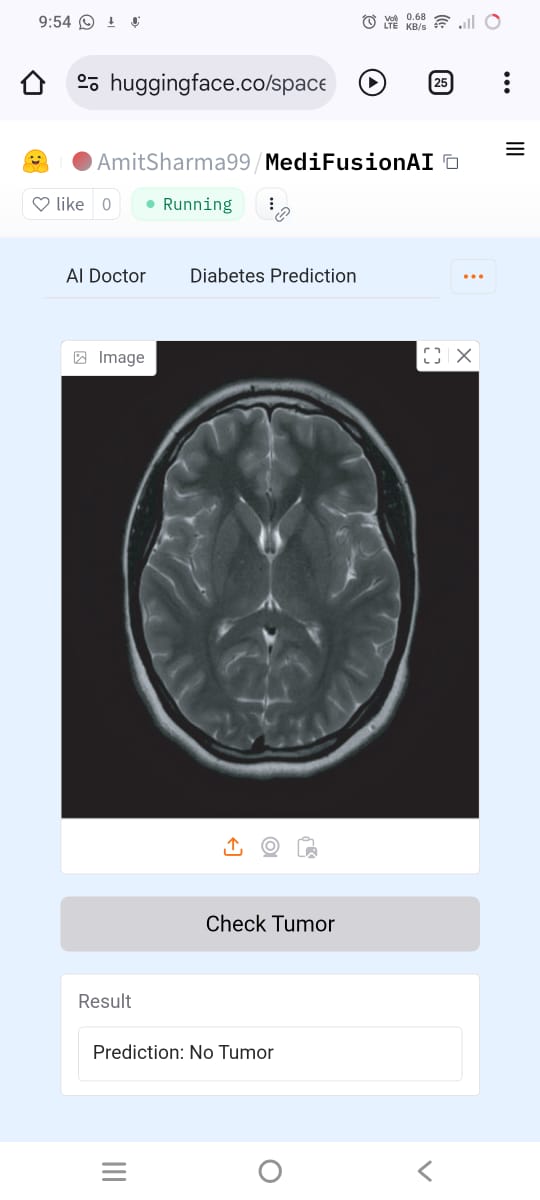

- Predicts diseases using ML models for Diabetes, Tumor Detection, and Heart Disease

- Integrated ML & DL models: Diabetes, Tumor (CNN), and Heart Disease